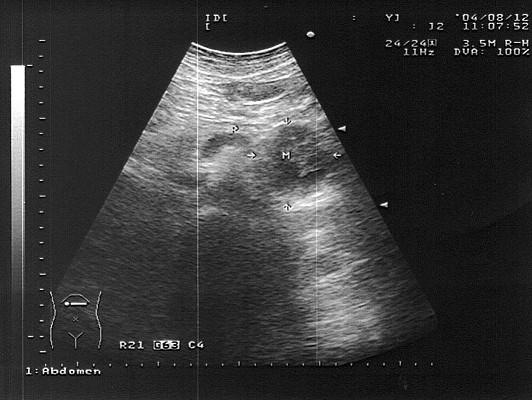

女,51岁,纳差、消瘦。结合超声声像图,诊断为?(?)A.胰腺癌B.腹膜后肿块C.胰岛细胞瘤D.胃癌E.胰腺炎

问题 女,51岁,纳差、消瘦。结合超声声像图,诊断为?(?)

选项 A.胰腺癌 B.腹膜后肿块 C.胰岛细胞瘤 D.胃癌 E.胰腺炎

答案 A